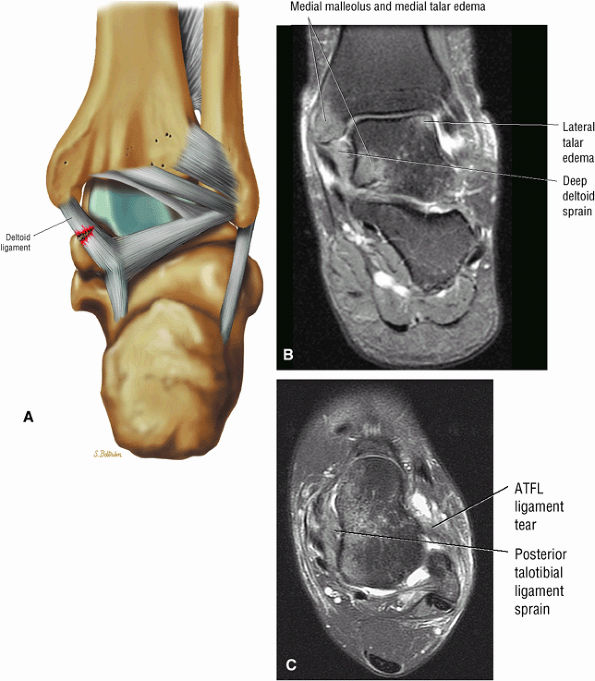

fascicle inserts onto the superior border of the calcaneona vicular ligament. The deep part of the deltoid, which is rectangular, consists of a small anterior component (the anterior tibiotalar ligament) and a strong posterior component (the posterior tibiotalar ligament) (Fig. 5.64). The posterior tibiotalar ligament represents the strongest part of the entire medial ligament complex. The deep portion of the deltoid ligament, covered by synovium, is intra-articular.

The syndesmotic ligaments consist of the anterior syndesmotic or anterior inferior tibiofibular ligament and the posterior syndesmotic or posterior inferior tibiofibular ligament, the interosseous membrane, and the transverse tibiofibular ligament.

The deltoid ligament consists of superficial and deep layers.